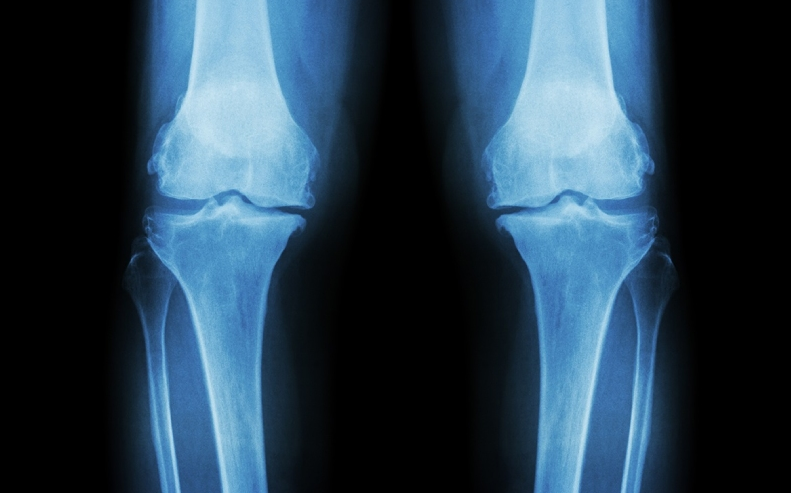

Gãy xương ở trẻ em và tổn thương sụn tăng trưởng thường liên quan nhau. Mô xương đang phát triển gần các đầu xương của trẻ sẽ bị ảnh hưởng khi gãy sụn tăng trưởng. Do tình trạng gãy sụn tăng trưởng ở trẻ em có thể ảnh hưởng đến sự phát triển của xương, nhất là ở trẻ đang dậy thì nên việc chụp x-quang thường quy để chẩn đoán tổn thương sụn tăng trưởng và việc điều trị cần được tiến hành ngay lập tức.

Các sụn tăng trưởng là vùng sụn nằm trong các xương dài của cơ thể, gần các đầu xương lớn, ví dụ như xương đùi, xương bàn tay, xương mác và xương đòn ở cẳng tay. Những sụn tăng trưởng đặc biệt này là những phần xương cứng lại cuối cùng của trẻ và rất dễ bị tổn thương.

Chụp X quang: Bác sĩ có thể yêu cầu cho trẻ chụp X-quang sụn tăng trưởng để xác nhận tình trạng gãy mảng tăng trưởng.

Khám lâm sàng rất quan trọng trong chẩn đoán gãy sụn tăng trưởng vì không thể nhìn thấy một số vết gãy sụn tăng trưởng không di lệch trên phim chụp X-quang.

Ngoài ra, so với xương của người lớn thì xương của trẻ em có cấu trúc khác và gãy theo các kiểu khác nên nhìn trên phim chụp X-quang, bác sĩ dễ bỏ sót một số thay đổi nhỏ cho thấy gãy sụn tăng trưởng. Ngược lại, có một số trường hợp trông giống như gãy xương nhưng bác sĩ lại xác nhận là xương phát triển bình thường hoặc sụn tăng trưởng bình thường.